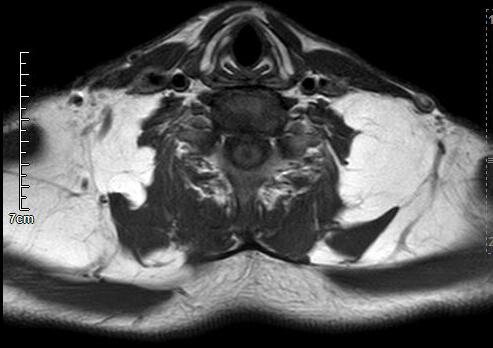

马德龙病的影像表现为颈项部等处脂肪组织蓄积增厚,可累及皮下或肌肉间隙,脂肪蓄积处没有包膜形成,蓄积脂肪内可有线状或网状纤维间隔,病变常常左右对称,颈部肌肉可受压、变细,蓄积脂肪组织内可有钙化或骨化。